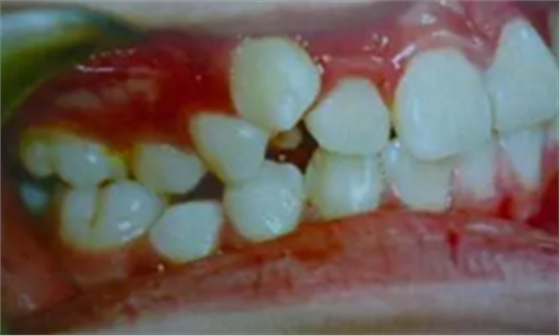

牙齒需要矯治的患者,往往牙齒和排列和咬合關(guān)系多會(huì)出現(xiàn)錯(cuò)亂,那些錯(cuò)亂的牙齒即使不拔除,它也是沒有功能的,因?yàn)樗蛯?duì)頜的牙齒咬不上。

并且,這些排列不正常的牙齒很難清理干凈,容易在它的周圍存留很多食物殘留,久而久之就形成蛀牙,最后也是一拔了之。我們醫(yī)生拔牙的時(shí)候有一定選擇的,一般是拔除那些壞牙、沒有功能的牙。